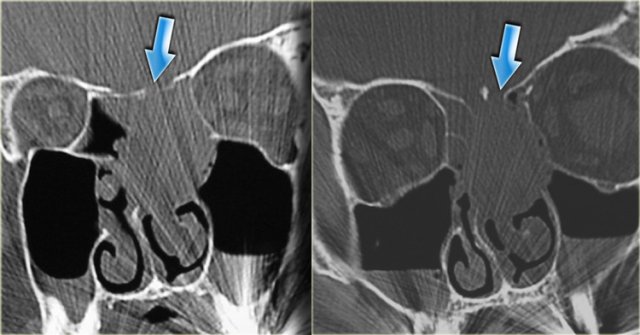

Sinonasal carcinoma Sinonasal carcinoma

This is the corresponding CT, performed not to make the diagnosis, but to assess the condition of the adjacent bony structures, especially the sphenoid sinus.

Also, it serves to guide the endoscopist for intraoperative biospy.

There is extensive destruction of the skull base.

The coronal image illustrates a normal foramen rotundum on the left (yellow arrow), which on the right has been obliterated by soft tissue.

There is extensive bone destruction, and a possible area for biopsy is indicated by the blue arrow.

At biopsy the diagnosis of a spindle cell carcinoma was made.